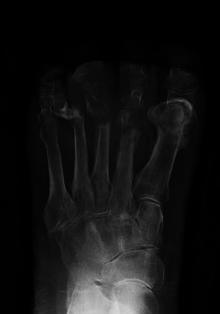

Extensive osteomyelitis of the forefoot

The diagnosis of osteomyelitis is complex and relies on a combination of clinical suspicion and indirect laboratory markers such as a high white blood cell count and fever, although confirmation of clinical and laboratory suspicion with imaging is usually necessary.[21]

Radiographs and CT are the initial method of diagnosis, but are not sensitive and only moderately specific for the diagnosis. They can show the cortical destruction of advanced osteomyelitis, but can miss nascent or indolent diagnoses.[21]

Confirmation is most often by MRI. The presence of edema, diagnosed as increased signal on T2 sequences, is sensitive, but not specific, as edema can occur in reaction to adjacent cellulitis. Confirmation of bony marrow and cortical destruction by viewing the T1 sequences significantly increases specificity. The administration of intravenous gadolinium-based contrast enhances specificity further. In certain situations, such as severe Charcot arthropathy, diagnosis with MRI is still difficult.[21] Similarly, it is limited in distinguishing bone infarcts from osteomyelitis in sickle cell anemia.[22]